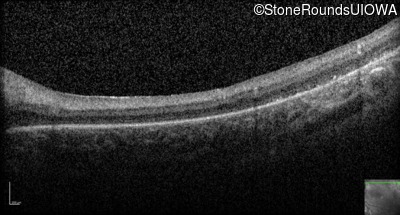

Optical Coherence Tomography - Right -

No Light Perception

Exemplar

Optical Coherence Tomography - Left -

Light Perception